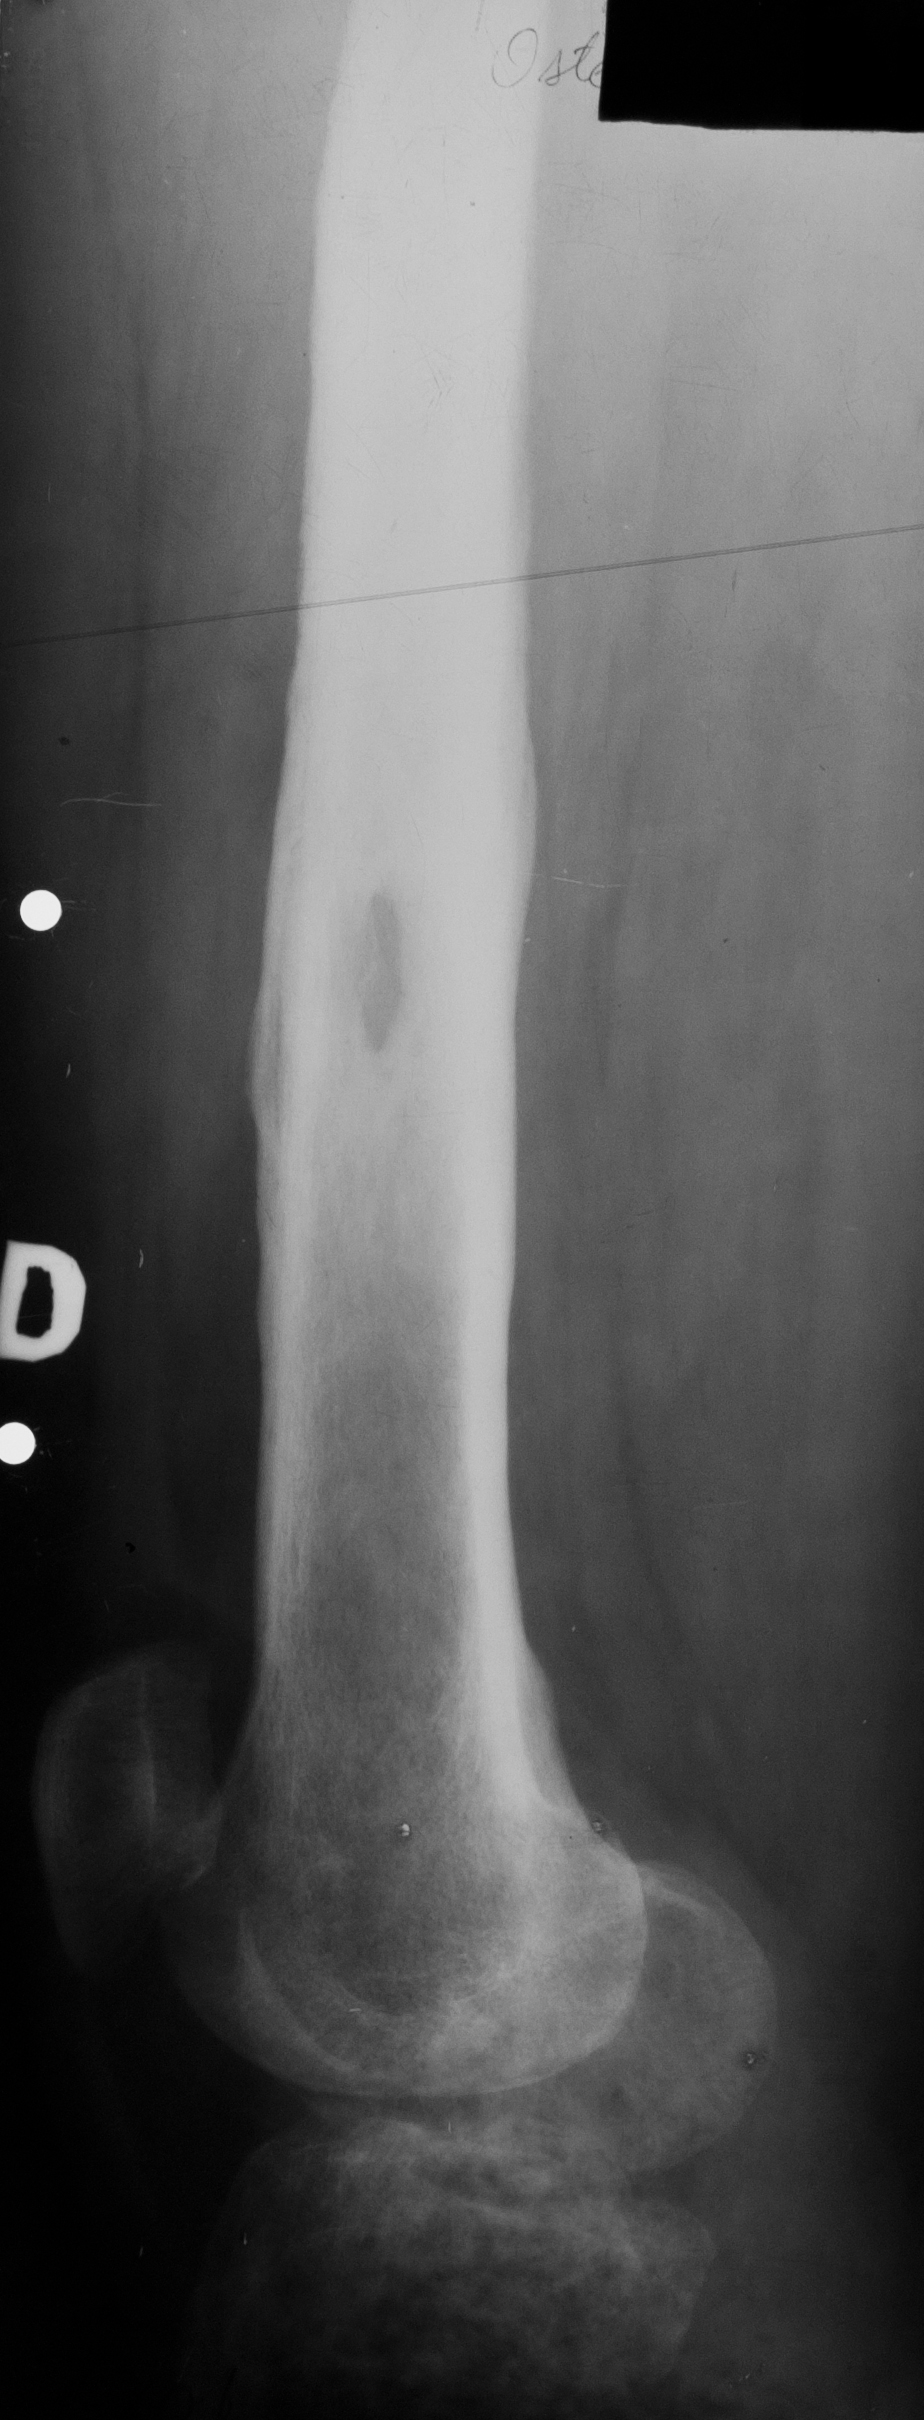

Osteomiolita cu sechestru

Radiografie de femur, undeva la nivelul diafizei, arie de osteoliza cu mic sechestru osos cu zona de osteoporoza in vecinatate si cu reactie periostala

Hiperostoza tibiei, care e de dimensiuni mari, fara canal medular, deci cu proces de scleroza endostala si cu ingrosarea semnificativa undeva in treimea superioara si mijlocie a diafizei, ca si consecinta a osteomielitelor cronice